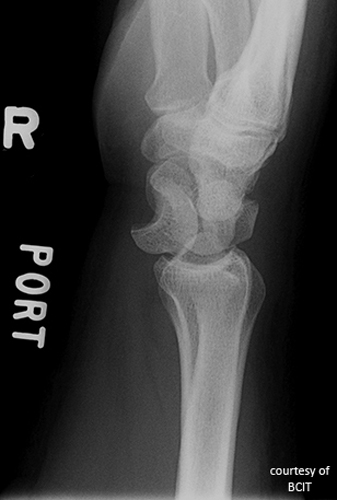

What does a 'spilled teacup' appearance indicate on lateral wrist imaging?

Lunate dislocation.

What causes lunate dislocation and what are its features?

FOOSH injury; volar displacement, loss of articulation with capitate and radius.

What is the treatment and complication of lunate dislocation?

Reduction, immobilization, often surgery; complications include arthritis and wrist instability.

The alignment of the third metacarpal, capitate, lunate, and radius on a lateral view (the “teacup” effect).